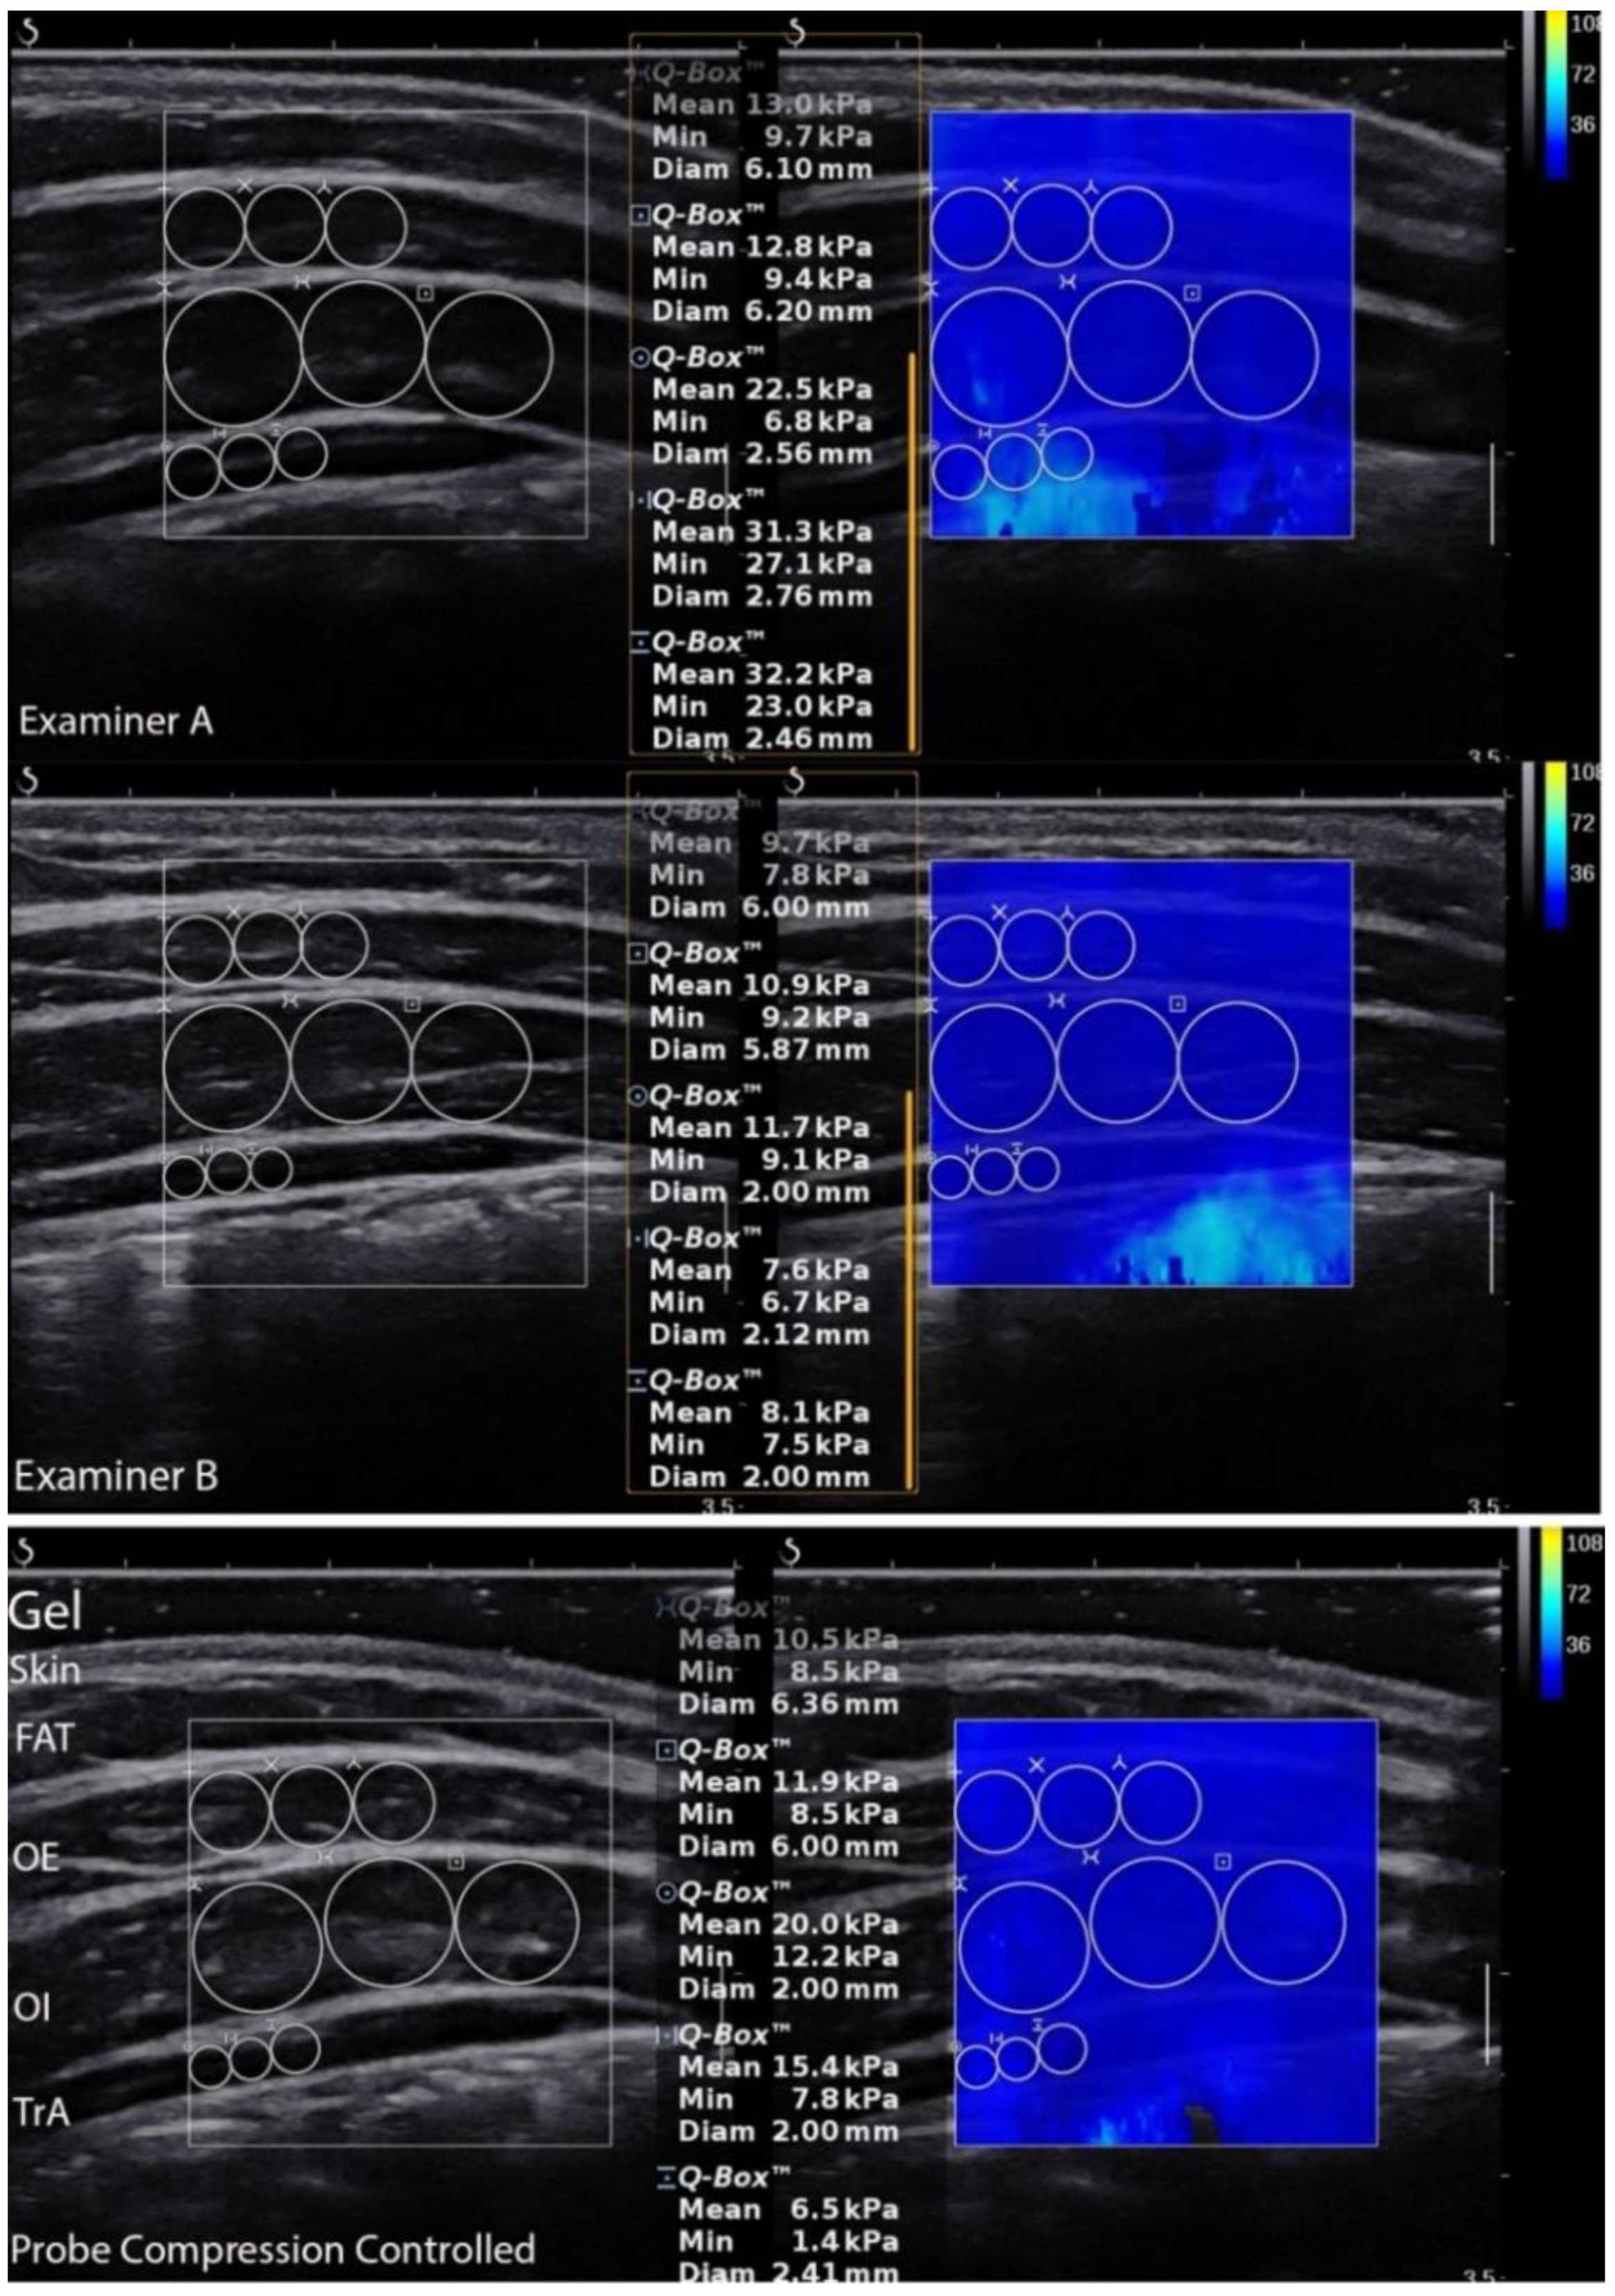

2.4. Equipment and Data Analysis

2.5. Measurement Procedures